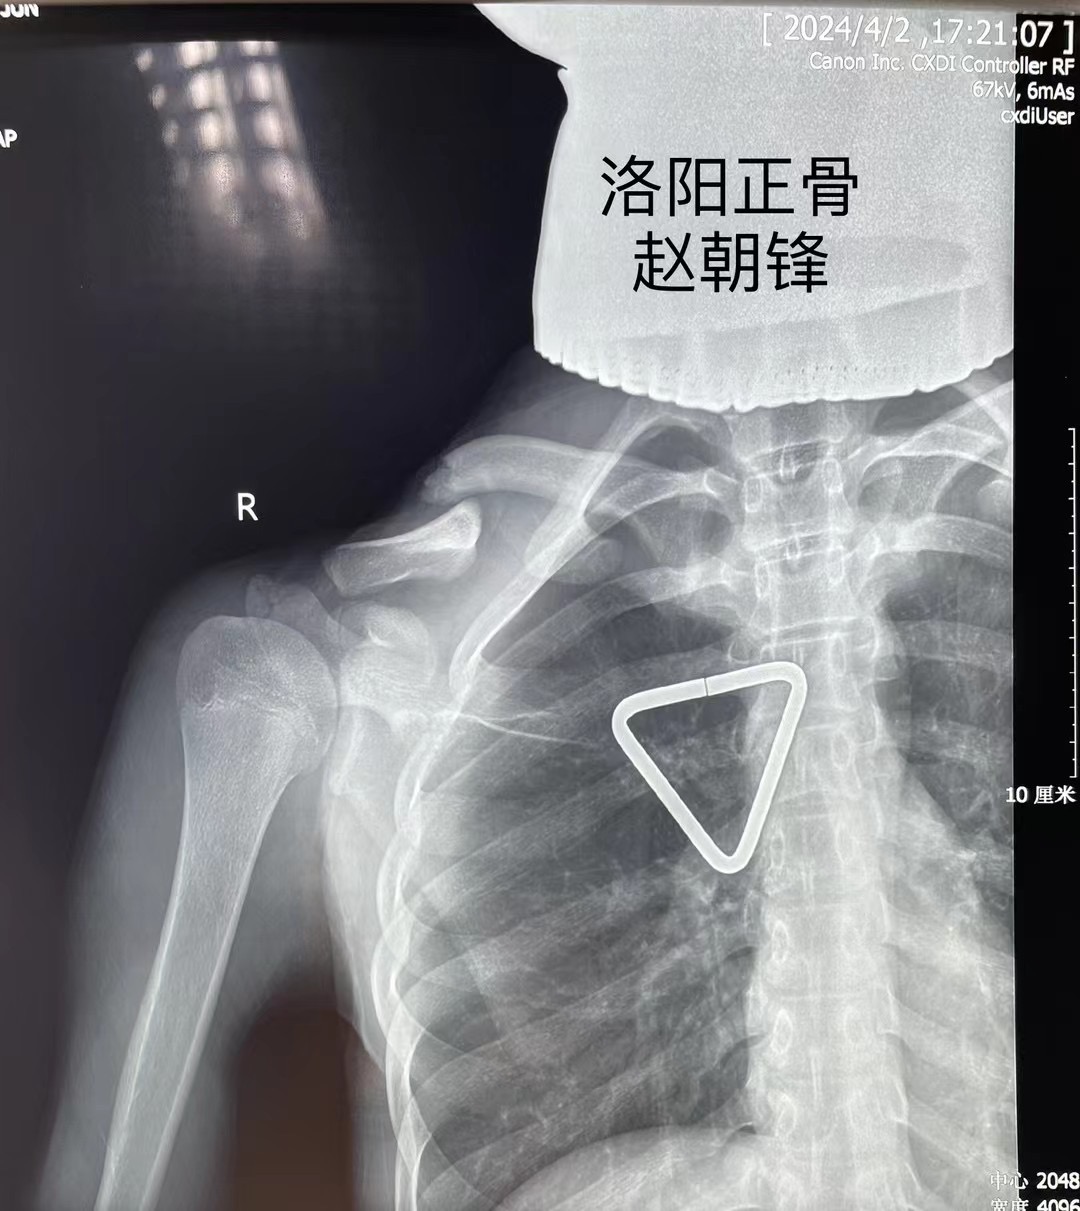

谢先生的孩子,小谢同学今年15岁,在跑着玩耍时摔倒,造成右肩部肿痛、活动受限,拍片显示右锁骨骨折,错位明显,辗转多家医院就医,均表示要开刀,放入钢板固定,但是小谢同学将来要报考军校,多年梦想,不想因为一朝骨折就放弃,于是慕名来到我院,找到手法正骨二科(微创正骨二科)主诊组长赵朝锋,经过制定详细的手术方案,主诊组长赵朝锋建议采用“手法复位、闭合穿针”治疗,这种方法具有创伤小、愈合快、功能恢复好、无皮肤切口瘢痕等诸多优点,在术后换药时,谢先生仔细观察了孩子的伤口:“没有切开皮肤,只在皮肤上留下了几个小眼,效果真好!”